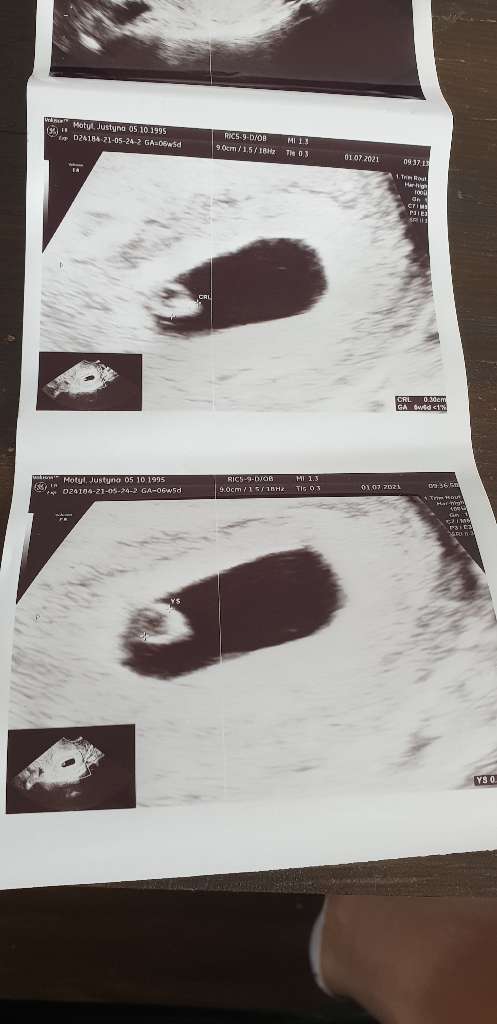

Dziewczyny jestem po pierwszej wizycie lekarz kazał mi wziąść większą dawkę letroxu z 50 na 75 , widziałam 3mm szczęścia i już widziałam bijące serduszko ❤ nie sądziłam że będzie to tak szybko, lekarz dla mojego spokoju przepisał mi duphaston 2x1 , już się uspokoiłam ale od rana nic nie dałam rady przełknąć 🙈 wg @ 6+5 a USG 5+6 jakim terminem bardziej sie sugerować? 😊 jestem dobrej myśli 🥰

Załączniki

• b6620a2b-4d49-4a11-9706-98f1ce53c256.jpg

b6620a2b-4d49-4a11-9706-98f1ce53c256.jpg

47,3 KB · Wyświetleń: 83